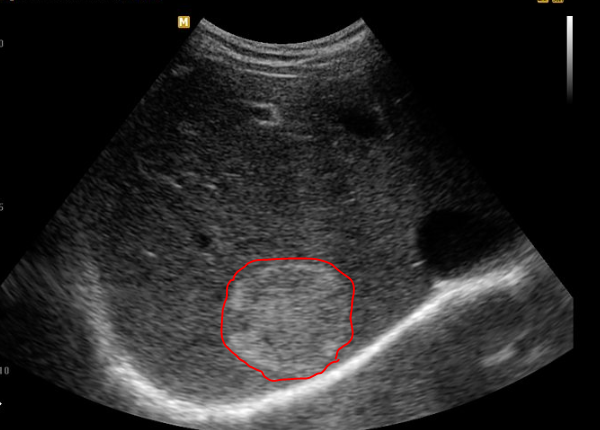

1. Ultrasound Scan

They typically appear white on ultrasound scan , of course not everything white is a liver hemangioma. Many hemangiomas are discovered incidentally on ultrasound.